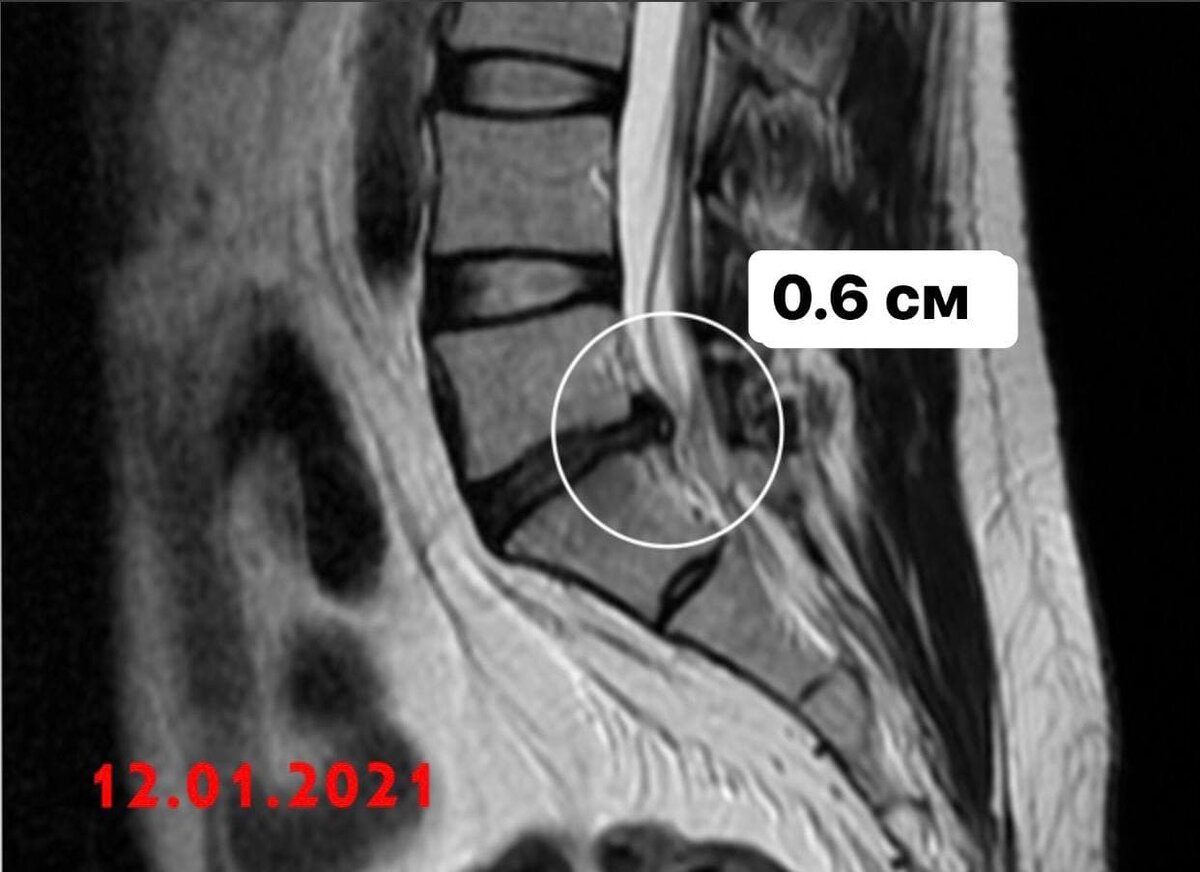

3) 12.01.21- L5S1- 6 мм. Без операции.

МРТ от января - грыжа 0.6 см

Январь 2021

РЕЗОРБЦИЯ! Грыжа поддалась!

Огромный сантиметровый кусок грыжи - растворился, был съеден макрофагами, и грыжевые ворота (дырка на диске) стали закрываться, рубцеваться.

К тому времени - болей от самой грыжи уже не было, и не было провокаций с моей стороны к этому - носил корсет, не поднимал ничего тяжелого, не наклонялся! Много и аккуратно ходил!